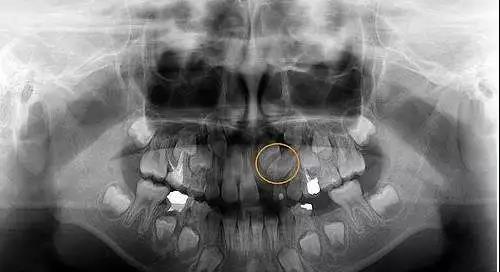

齿槽骨膜炎是由于齿槽和齿根之间的骨膜炎发生炎症。可以分为分为化脓性和非化脓性和弥散性三种,按病程又可分为急性和慢性。在幼驹和青年马驹比较多见,一般是第三和第四臼齿。多表现为咀嚼障碍,患部齿龈肿胀、疼痛,严重病例颊部或下颌出现肿胀。

副鼻窦炎是副鼻窦内的黏膜发生化脓性炎症而导致的窦腔内脓汁潴留。它的病因主要有化脓菌和异物侵入窦内;临近组织炎症蔓延;局部损伤;某些传染病。它的症状主要表现为吊鼻(就是流鼻涕,主要特点是一侧性吊鼻)和病窦变化。